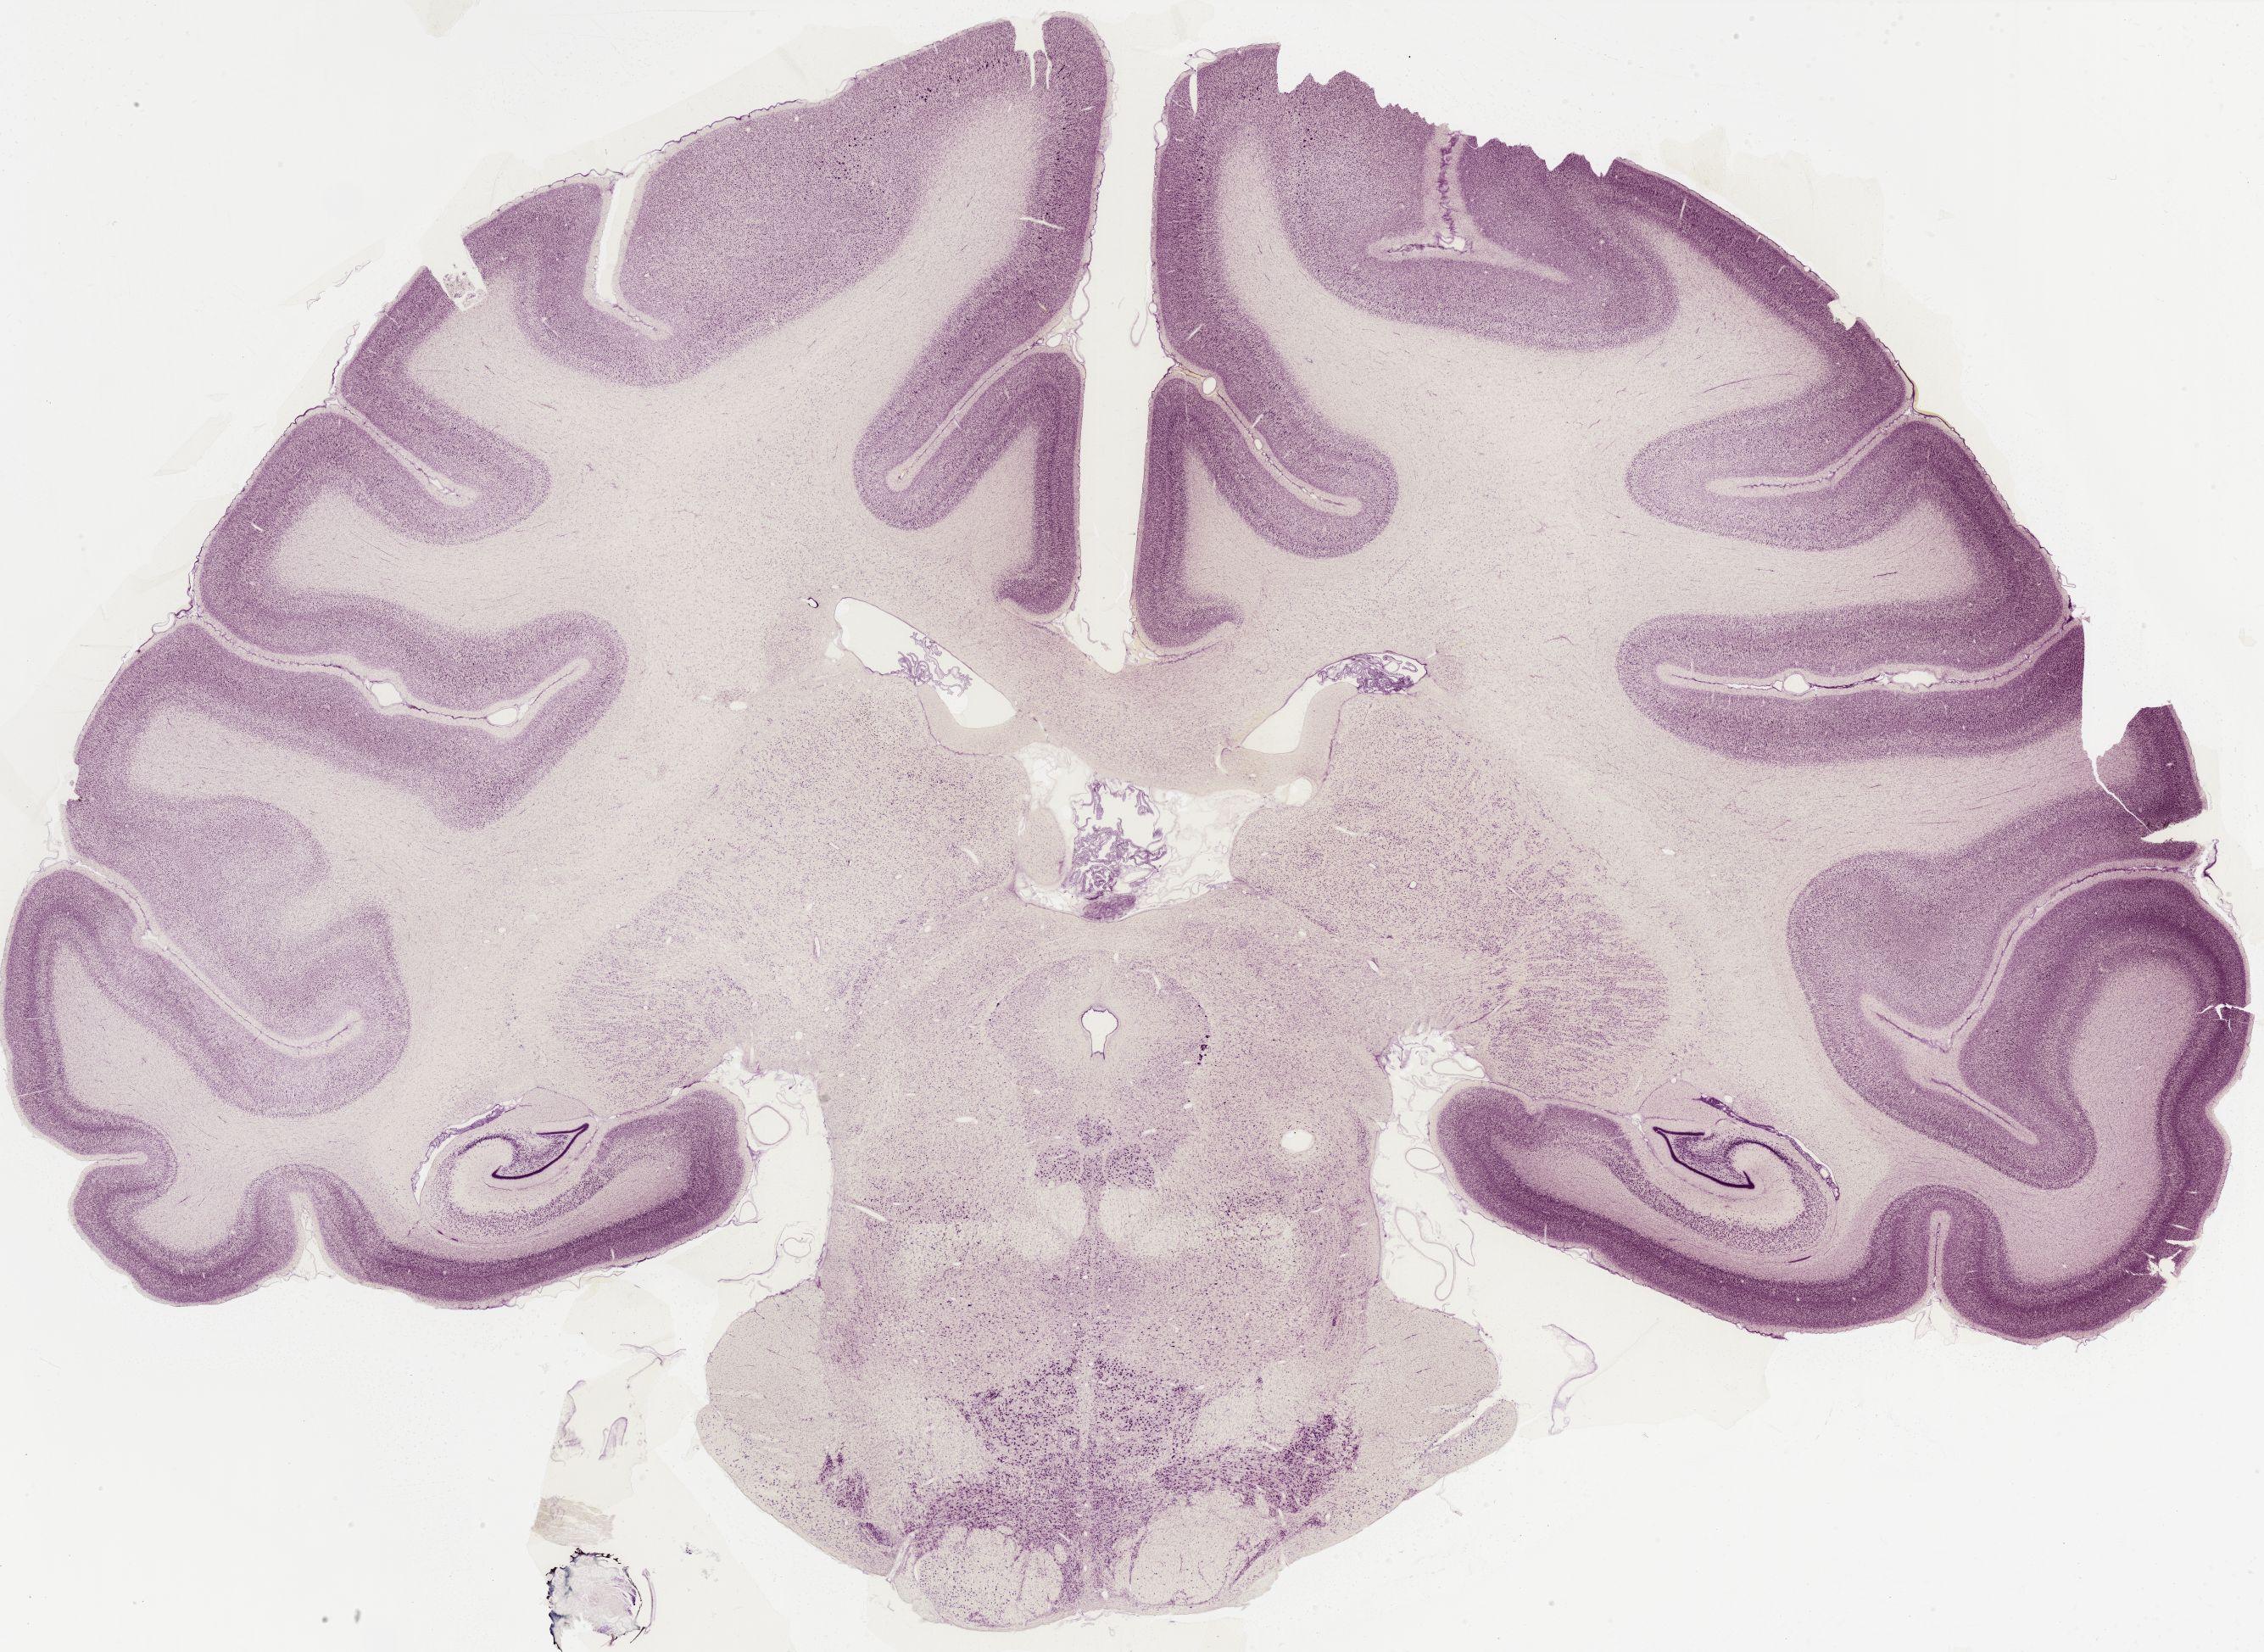

Datasets -> Macaca Mulatta -> Nissl, coronal, histo, Whole-Brain, adult [ Metadata ] · Source: Edward G. JonesDisplaying Sections 1 thru 40 of 56 Sections for this DatasetPages: 1 2 1339 - labeled 1301 - labeled 1251 - labeled 1201 - labeled 1151 - labeled 1102 - labeled 1051 - labeled 1040 - labeled 1020 - labeled 1006 - labeled 1001 - labeled 0982 - labeled 0975 - labeled 0958 - labeled 0951 - labeled 0941 - labeled 0924 - labeled 0920 - labeled 0901 - labeled 0894 - labeled 0878 - labeled 0875 - labeled 0859 - labeled 0851 - labeled 0845 - labeled 0824 - labeled 0823 - labeled 0801 - labeled 0800 - labeled 0785 - labeled 0781 - labeled 0771 - labeled 0770 - labeled 0732 - labeled 0721 - labeled 0720 - labeled 0701 - labeled 0682 - labeled 0680 - labeled 0666 - labeledPages: 1 2